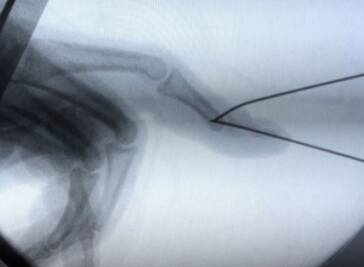

第一枚克氏针